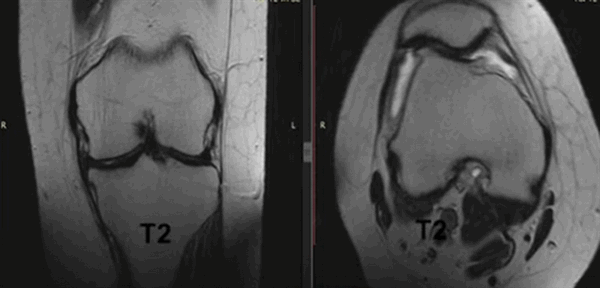

При МРТ получают серии монохромных снимков анатомической области в аксиальной, сагиттальной и фронтальной плоскостях. При изучении изображений врач видит контуры различных элементов сочленения. Расшифровка МРТ-снимка коленного сустава подразумевает оценку сканов в сравнении с нормой. МР-томограммы называют срезами, поскольку изображения производят послойно, с шагом 1-2 мм. Врач последовательно изучает анатомическую зону на предмет соответствия всех структур норме. В процессе расшифровки фото обращают внимание на качество визуализации элементов, четкость контуров, присутствие зон измененного МР-сигнала (гипер- или гипоинтенсивного) в различных режимах сканирования (Т1 ВИ, Т2 ВИ, ДВИ, подавление жира).

МР-снимок коленного сустава в режиме Т2, контузия кости

Варианты просмотра коленного сустава при МР-сканировании в разных проекциях (Т2 ВИ)